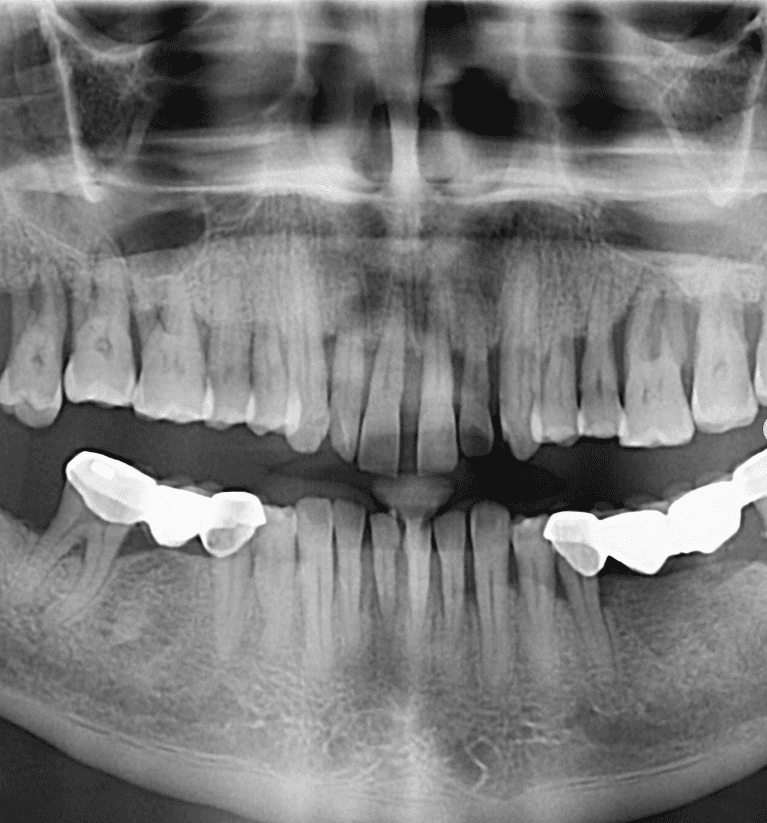

Upper & Lower, All on 4 fixed implant teeth with finals. Patient went home with temp fixed teeth the same day.